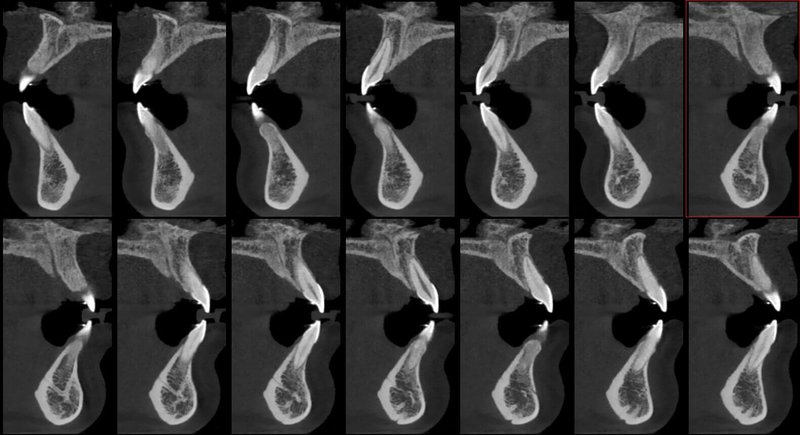

- Мощная диагностика

- Технология HR от Newtom

КОМПЛЕКСНЫЙ ГИБРИДНЫЙ КЛКТ ДЛЯ 2D/3D ВИЗУАЛИЗАЦИИ. ИЗОБРАЖЕНИЯ В ВЫСОКОМ РАЗРЕШЕНИИ С ЗАХВАТОМ МЕЛЬЧАЙШИХ ДЕТАЛЕЙ

GIANO HR – универсальное обновляемое устройство от NewTom для всех задач, связанных с радиографией. Благодаря полному диапазону опций 2D и 3D исследования для стоматологии оно предлагает множество особых трехмерных обследований для челюстно-лицевой хирургии, оториноларингологии и осмотра шейного отдела позвоночника. Визуализация только наивысшего качества с технологиями и опытом NewTom

NNT – программное обеспечение NewTom, предоставляющее несколько специальных режимов применения для имплантологии, эндодонтии, пародонтологии, челюстно-лицевой хирургии и радиографии. Это мощное технологически новейшее устройство, разработанное, чтобы снимать и обрабатывать изображения в несколько простых шагов для получения информации, необходимой для конкретного подробного диагноза пациенту. Продвинутое устройство, дающее врачу специальные инструменты для измерения анатомической области (расстояния и углы), нахождения нижнего альвеолярного нерва и замера объема верхних дыхательных путей.